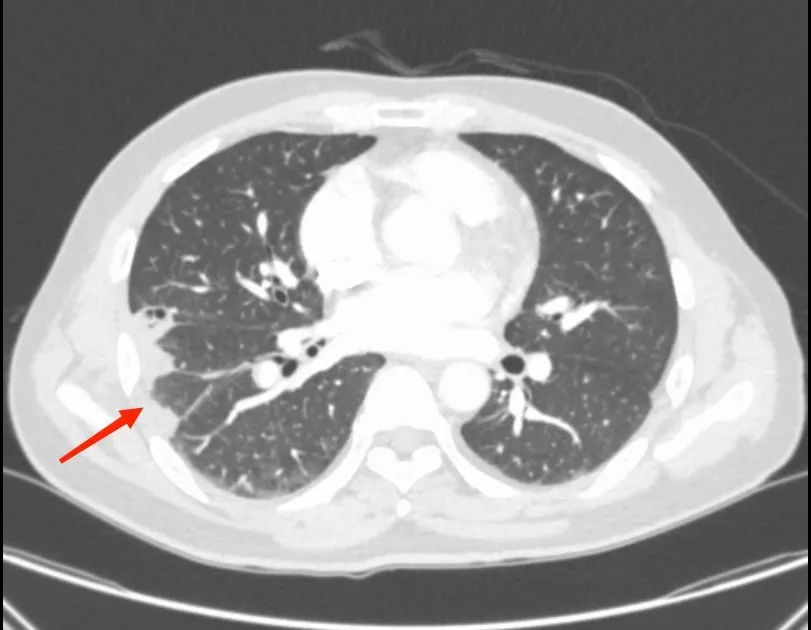

追问杨先生病史,他告知医务人员,今年5月就自行停用了糖皮质激素(肾病综合征的首选治疗用药)。为他重新使用糖皮质激素治疗后下肢水肿以及泡沫尿的症状逐渐缓解,但他的胸部CT提示右肺斑片状密度增高影,且各项血液检查感染指标均升高,结合患者有长期激素使用史(激素可导致免疫力低下,感染风险增高),主管医师考虑肺部存在细菌感染,遂给予抗生素治疗,但患者咳嗽、咳血痰症状并未得到缓解,复查CT提示肺部的炎症亦并未减少。

为尽快找到病因,肾内科紧急邀请肺部感染疾病专家团队——呼吸与危重症医学科三区专家前往会诊,专家对患者的肺部影像进行研究后,发现患者肺部病变部位周围可见“晕征”(环绕在病灶周围的磨玻璃影,而这对于感染来说最多见于肺曲霉菌病),专家们对曲霉菌感染在心中打了个问号。

考虑到杨先生病情较为复杂,呼吸与危重症医学科三区立即组织了多学科联合会诊。会上,专家们仔细回顾患者病史,他既往曾有颅内静脉血栓形成,且血脂远高于正常,高血脂的病人血液粘稠、流速缓慢,而这正是血栓形成的高危因素。杨先生的胸痛伴有咯血痰,肺部影像学改变为尖端指向肺门的阴影,除了肺部感染外,还有一个很重要且最容易让人忽视的疾病——肺栓塞!

不放过任何一个可疑因素,杨先生在医护人员的陪同下完善了肺动脉CTA检查,检查结果出来,果然是肺栓塞!杨先生肺部那一片片密度增高带有晕征的病变,以及抗感染治疗无效的疑点都得到了解释,是肺栓塞导致了肺梗死。